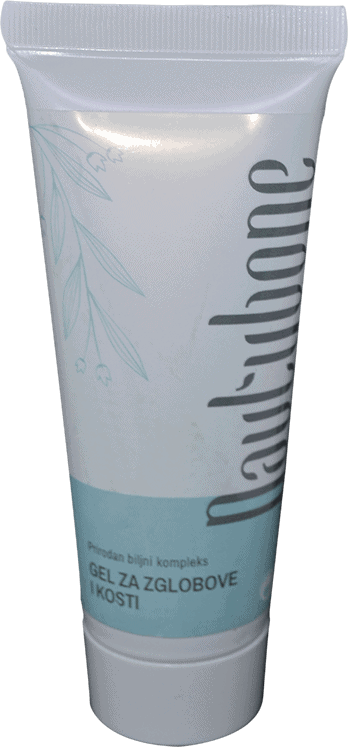

Nautubone - obnavlja zglobove i hrskavice

- regenerira tkivo hrskavice i zglobova

- instantno ublažava bol

- prirodan tretman bez nuspojava

- štedi vaš novac

- jednostavno za uporabu

Nautubone - obnavlja zglobove i hrskavice

- regenerira tkivo hrskavice i zglobova

- instantno ublažava bol

- prirodan tretman bez nuspojava

- štedi vaš novac

- jednostavno za uporabu